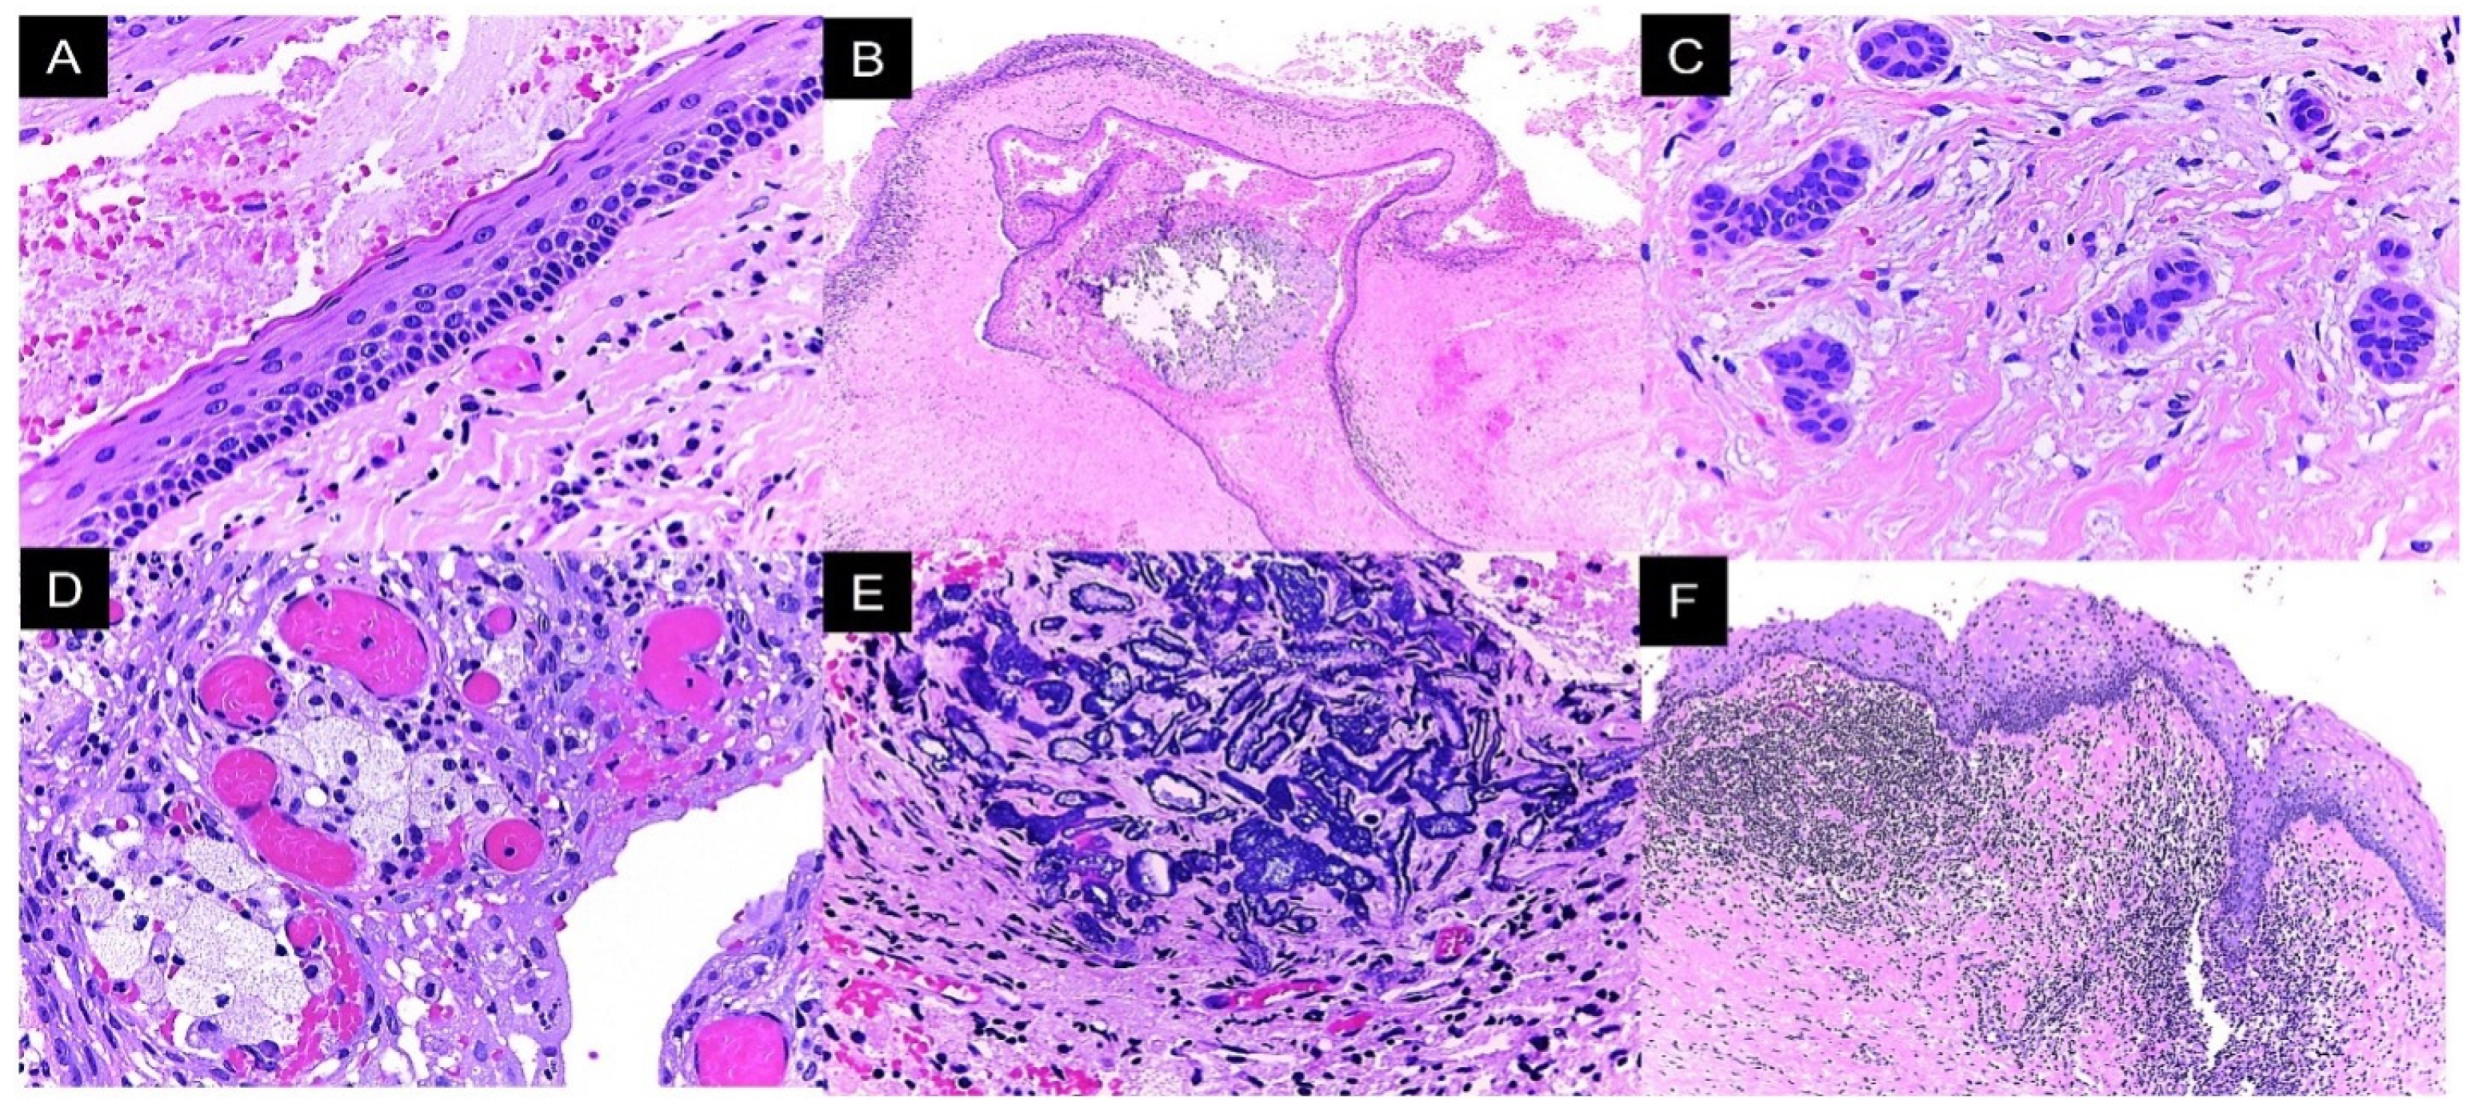

| OKC | Odontogenic keratocyst |

| BCC | Basal cell carcinoma |